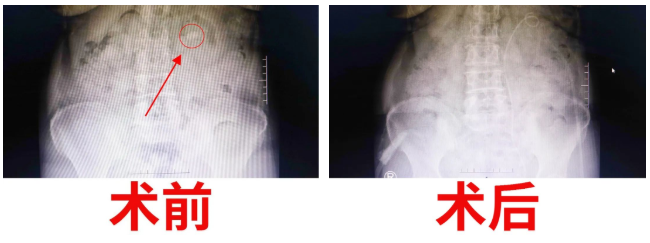

經(jīng)過泌尿外科醫(yī)護(hù)人員的密切觀察和精心護(hù)理,手術(shù)后的第三天,復(fù)查X光片,發(fā)現(xiàn)腎結(jié)石已消失得無影無蹤。“有了這樣先進(jìn)的機(jī)器,以及泌尿外科醫(yī)生團(tuán)隊(duì)高超的技術(shù),我們腎結(jié)石患者再也不用受病痛之苦了,這真是我們廣大腎結(jié)石患者的福音啊。”患者激動(dòng)的連聲道謝。一周后康復(fù)出院。